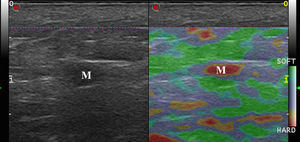

Tumores cutáneos malignosLa elastografía en los tumores malignos cutáneos muestra que tienen una rigidez superior al tejido circundante18 (fig. 5).

Dasgeb et al.25 estudiaron 55 pacientes con 67 tumores epiteliales, de los cuales 29 eran malignos (17 carcinomas basocelulares y 12 carcinomas espinocelulares) y 19 benignos. En este estudio, los SR de los tumores cutáneos epiteliales fueron superiores a 3,9, y en el caso de los tumores cutáneos benignos, todos presentaban un SR inferior a 3. En este estudio valores de SR entre 3,00 y 3,9 presentaron una sensibilidad y especificidad del 100% a la hora de diagnosticar una lesión cutánea como maligna.

En el caso del melanoma, en el estudio piloto de Botar et al.26 —que incluía 42 melanomas en 39 pacientes— estudiaron la SE y la vascularización mediante Doppler color de las lesiones.

Los melanomas presentaron hipervascularización con múltiples pedículos vasculares y mayor dureza en la SE que la piel adyacente. Así mismo, las lesiones más vascularizadas presentaron una mayor dureza.

Es bien conocido en la literatura que existe una correlación entre la neovascularización del melanoma y su pronóstico27,28, por lo tanto, la dureza lesional podría ser un factor pronóstico en el melanoma29.